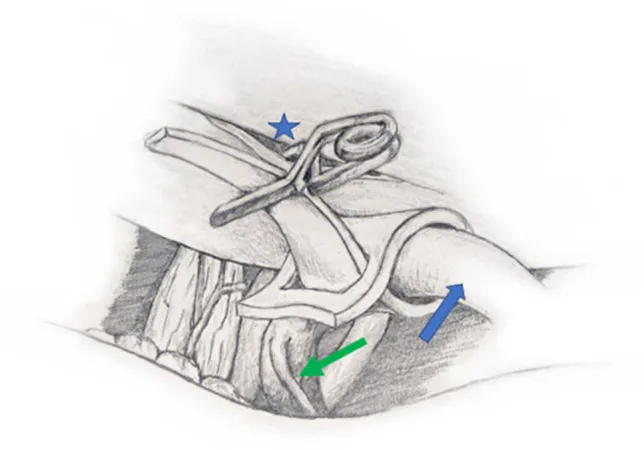

神经血管减压技术示意图,采用特氟龙桥,正面视图。A:显示使用一块特氟龙创建一个简单的特氟龙桥。B:展示相同技术附加支柱以进一步增加特氟龙和面神经之间的距离。

吊带环绕椎动脉并固定于颅底硬膜(内听道与颈静脉孔间硬膜袋,以Yasargil迷你夹固定)(图3)。

因此,松开迷你夹、稍放松吊带以降低穿支动脉的张力。随后用撕裂的特氟龙对小脑下前动脉进行减压。术后无并发症,汉娜的症状即刻完全缓解;10个月随访无痉挛,听力及面功能正常。